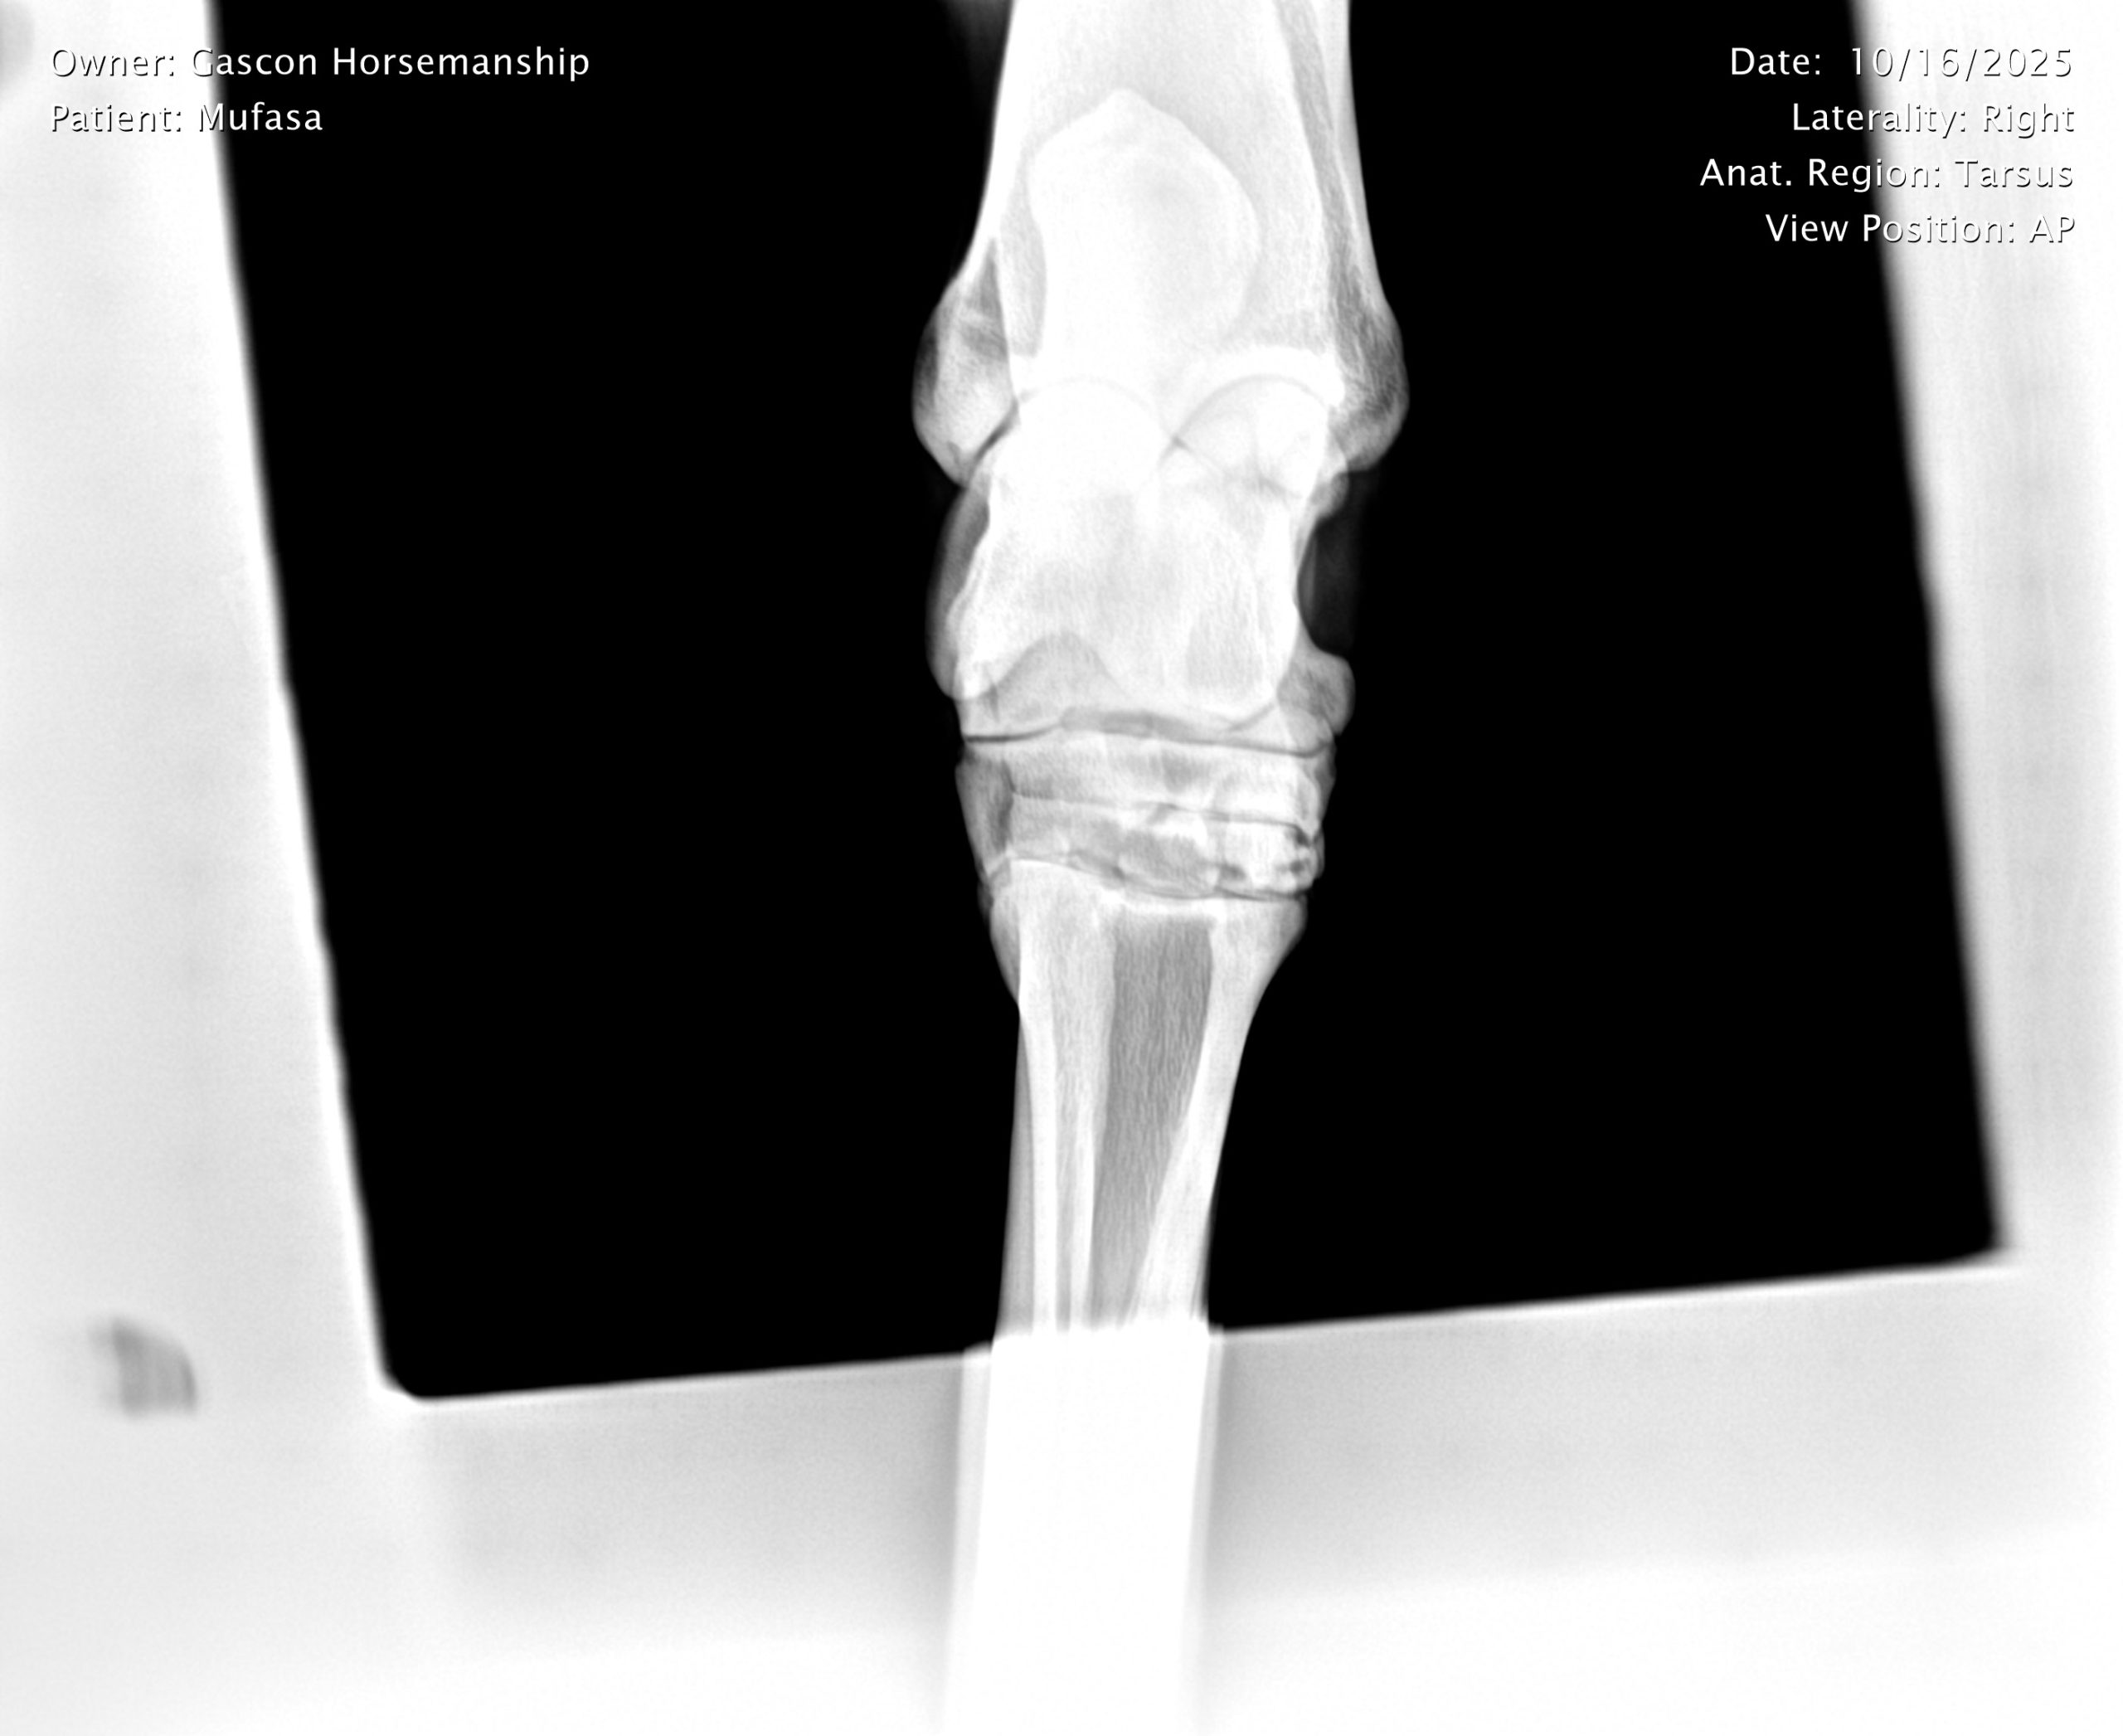

He already has a full pre-purchase exam on file, complete with 25 X-rays included in his album.